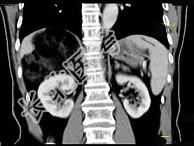

- 单项选择题男,59岁, 右侧腰背酸痛,CT检查如图所示, 应诊断为 ( )

A、右肾上腺腺瘤

B、右肾上腺转移瘤

C、右肾上腺髓样脂肪瘤

D、右腹膜后脂肪瘤

E、右肾血管平滑肌脂肪瘤